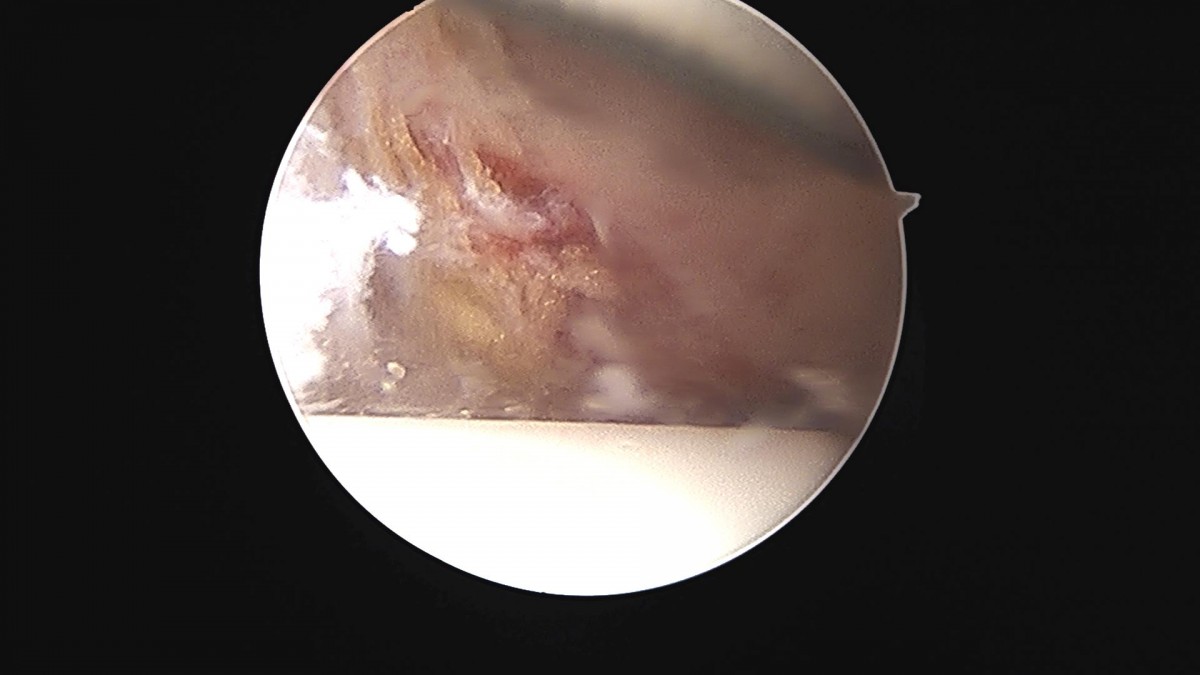

배우한원장님 발목인대봉합술 (4622)박채O 환자

작성자 최고관리자 댓글 0건 조회 1,226회 작성일 22-05-09 12:38